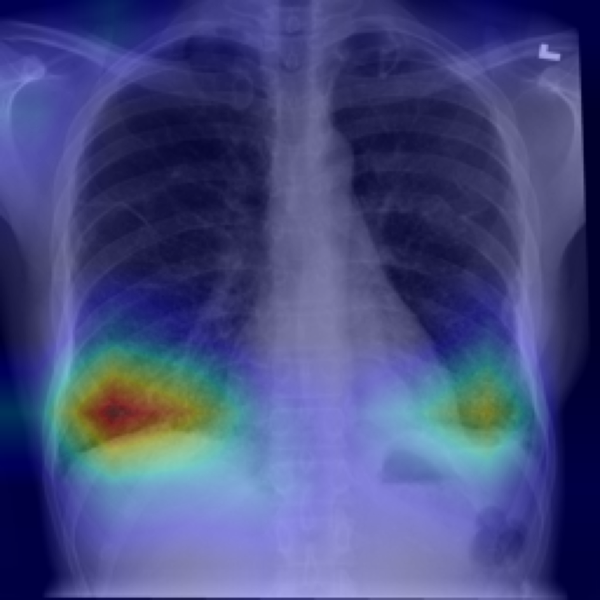

4.2.4 Grad-CAM heat activation map

Figures 33 and 34 show the two end-points ( and ) for one representative X-ray. The CNN‐based neutralizer leaves the hotspots largely intact and increases the male probability from to . In contrast, the ViT neutraliser erases the right-lung focus and tightens the left-lung patch, pushing the classifier to an almost certain male prediction (). Figure 35 presents the full -sweep for the ViT-based neutralizer, confirming that the highlighted sex evidence fades smoothly and the model’s male probability falls toward 0.5 once .